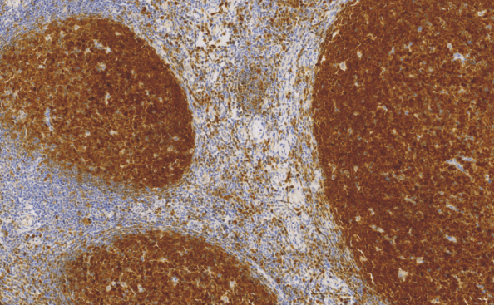

B Cell Specific Octamer Binding Protein-1(BOB-1)鼠抗人B 细胞特异性八聚体结合蛋白-1单克隆抗体

B细胞特异性八聚体结合蛋白-1,是淋巴细胞特异性转录共激活蛋白。一般情况下,BOB-1与Oct-1和Oct-2相互作用,表达于B细胞的细胞核和浆细胞中,通常BOB-1的表达强于Oct-2。这些抗体联合应用,可以应用于经典霍奇金淋巴瘤与大B细胞淋巴瘤的鉴别诊断,据报道,一些T细胞淋巴瘤阳性表达BOB-1。

- 阳性部位:胞质,胞核